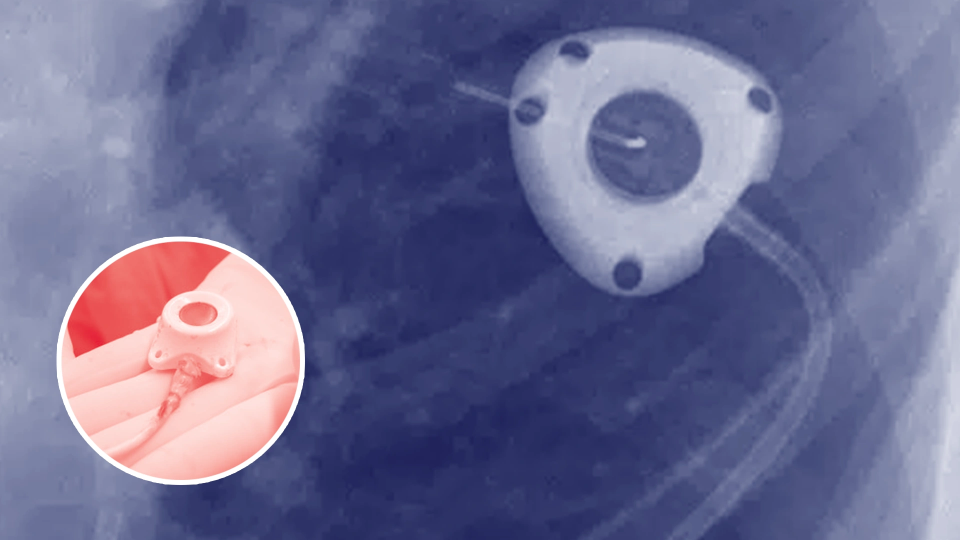

The Bard PowerPort is a small medical device implanted under the skin, primarily used for patients requiring long-term IV therapy or chemotherapy. It allows for easy and repeated access to veins.

Plaintiffs claim that due to design and material defects, the PowerPort’s catheter tube can crack or break apart, leading to: